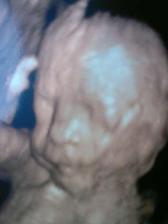

5.7. 4D ultrazvuk...nádherný zážitek:o)